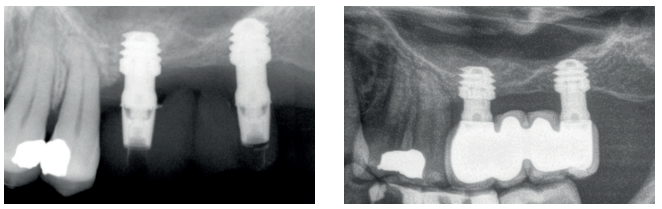

En las Figuras 2- 19 se muestra uno de los casos incluidos en el estudio.

pérdida ósea que presenta, además de una movilidad grado III.

imagen apical en la raíz distal. Se decide proceder a la extracción y regeneración con Endoret-PRGF además de la inserción de

un implante en la zona correspondiente al molar 27.